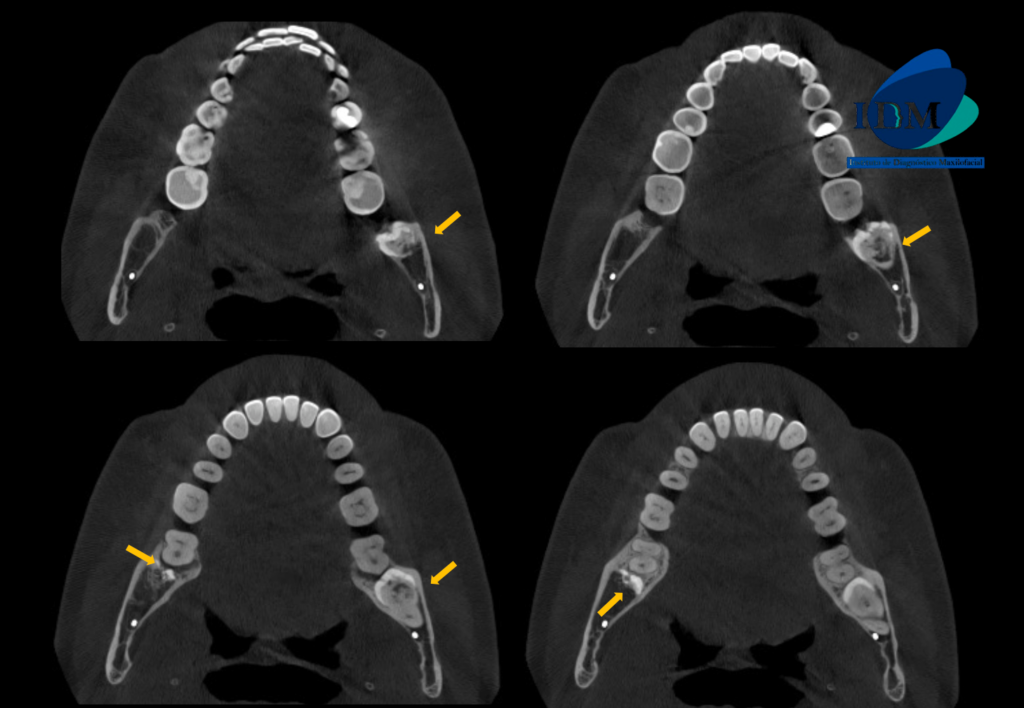

A la evaluación de la tomografía volumétrica (cone beam) en los cortes axiales (Figura 2), transaxiales (Figura 3) y tangenciales (Figura 4) se observa una reabsorción coronaria y radicular externa en tercio cervical de raíz distal (ameloclasia). Así como el remanente dentario de la pieza 48.

CORTES AXIALES